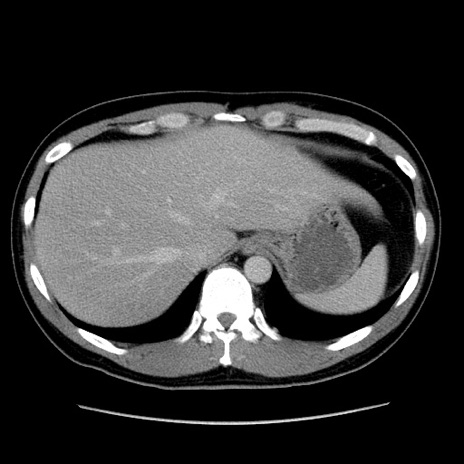

冠状断像

【症例】30歳代男性

【主訴】腹痛、嘔吐

【現病歴】昨晩から突然の腹痛あり、その後嘔吐、軟便も出現。腹痛が改善しないため救急搬送となる。2日前にしめ鯖の食事歴あり。

【身体所見】意識清明、苦悶様、BP 135/90mmHg、BT 35.7℃、腹部:平坦、やや硬、心窩部〜臍部に自発痛、圧痛あり、筋性防御+、反跳痛-

【データ】WBC 8100、CRP 0.57